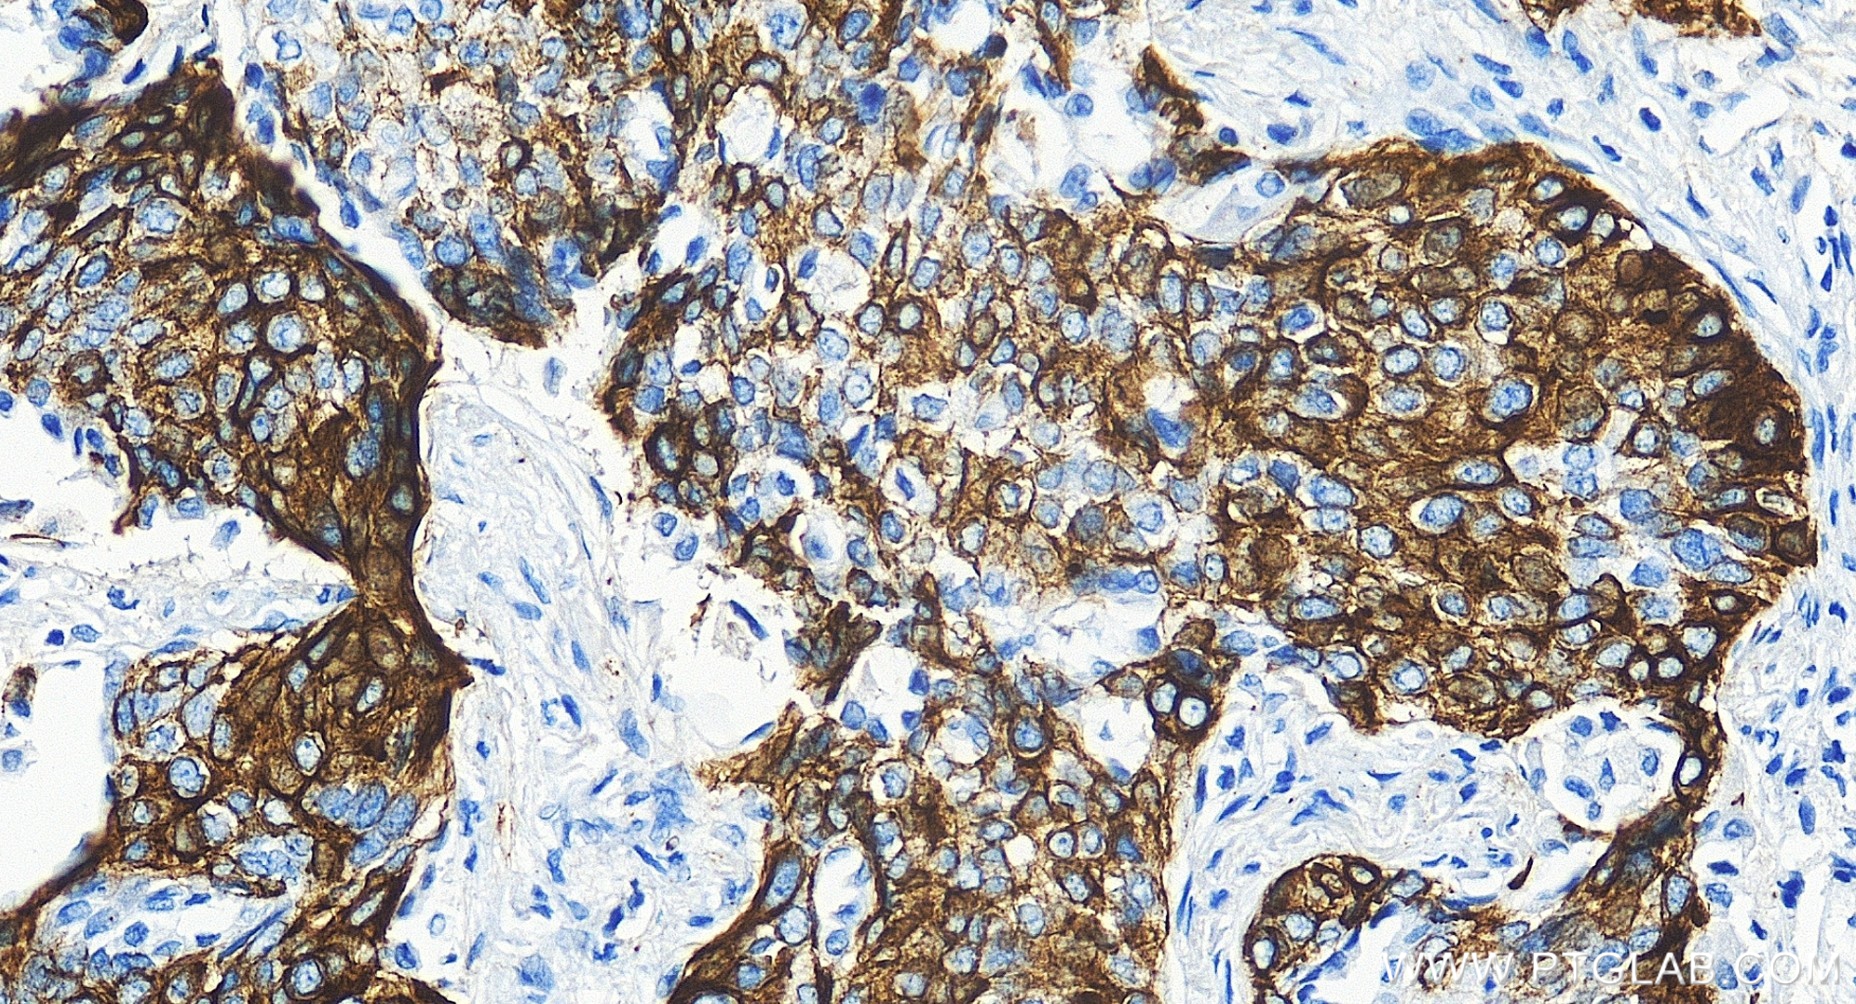

83379-1-PBS targets Cytokeratin 14 in WB, IHC, IF-P, Indirect ELISA applications and shows reactivity with human, mouse, rat samples.

Cytokeratin 14, one of about 20 different cytokeratin isotypes of human cells, is the intermediate filament protein characteristic of epithelial cells. Cytokeratin 14 is expressed in the basal compartment of all stratified squamous epithelia. In various kinds of human tumors, the appearance and increasing expression of Cytokeratin 14 were strikingly associated with higher grade and stage of carcinoma, with varying degrees of unfavorable prognosis. In lung squamous cell carcinoma(LSCC), Cytokeratin 14 was expressed in the tumor cell nests showing stromal invasion with fibrosis and lymph node metastases, indicating that Cytokeratin 14 involved in proliferation and metastasis of LSCC. Cytokeratin 14 expression is sometimes used in diagnosis of myoepithelioma1 and intraductal vs. invasive ductal carcinoma of the breast.